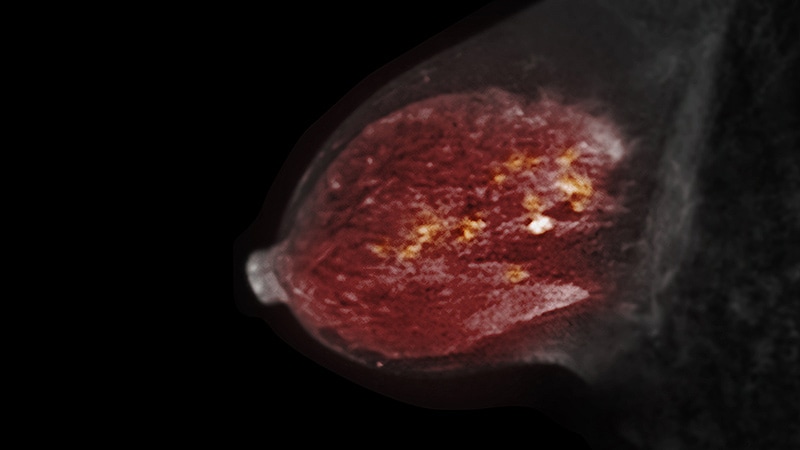

Despite improvements in access to health coverage under the Affordable Care Act (ACA), racial disparities in breast cancer mortality rates persist and the underuse of advanced breast imaging may be one culprit, experts say.

Breast MRI is known to provide the highest rate of breast cancer detection among commonly used imaging options, with a sensitivity ranging from 81%­–100%. That’s about twice as high as the sensitivity range for mammography after factoring in breast density.

For Black women in particular, studies show nearly a quarter (23%) who develop breast cancer are diagnosed under the age of 50 compared with 16% of White women. Black women are also more likely to develop more aggressive, premenopausal breast cancers, including triple-negative breast cancer, that are more easily detected on MRI.